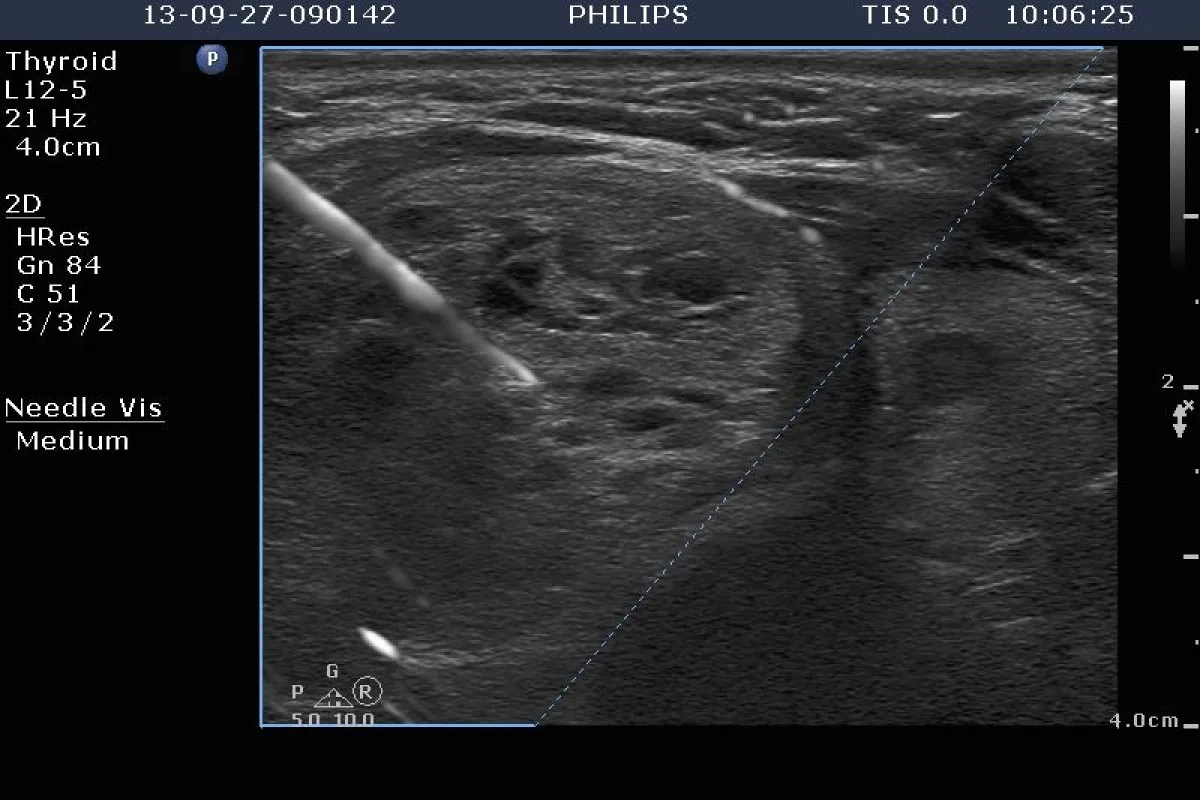

Dlaczego USG tarczycy jest niezbędnym uzupełnieniem badania krwi?

Poza badaniami krwi, niezwykle ważnym elementem diagnostyki autoimmunologicznych chorób tarczycy jest badanie ultrasonograficzne (USG) tarczycy. USG pozwala lekarzowi "zobaczyć" tarczycę, ocenić jej strukturę, wielkość, unaczynienie oraz wykryć ewentualne zmiany. W przypadku choroby Hashimoto, USG często wykazuje charakterystyczne cechy zapalenia, takie jak niejednorodna echogeniczność miąższu, zmniejszenie lub powiększenie gruczołu, czy obecność drobnych guzków. Jest to kluczowe uzupełnienie wyników badań krwi, ponieważ pozwala na pełniejszy obraz stanu tarczycy i potwierdzenie diagnozy.